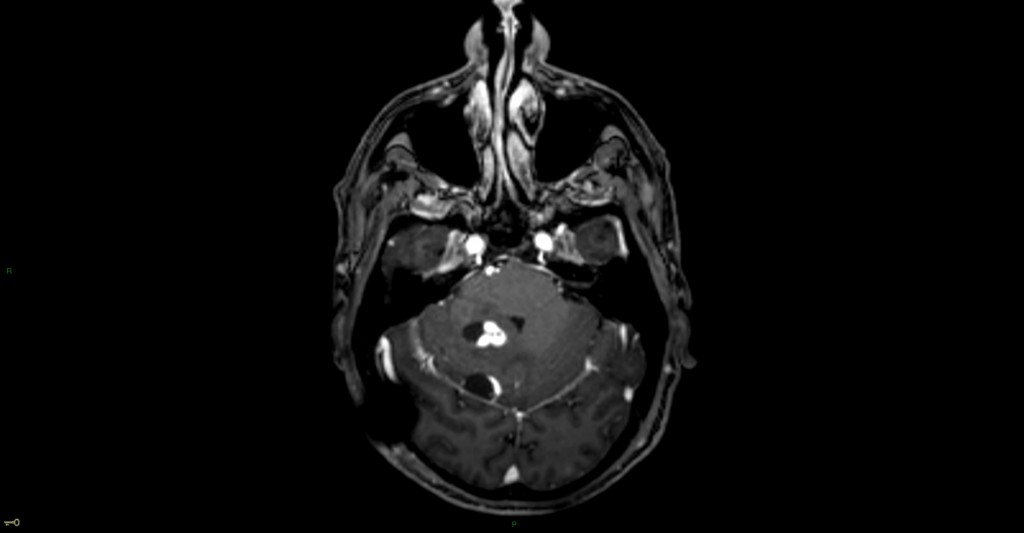

Hémangioblastome dans le cadre d’une maladie de Von Hippel Lindau

Oedème péri-lésionnel marqué en FLAIR à l’étage encéphalique

Souvent nodulaire